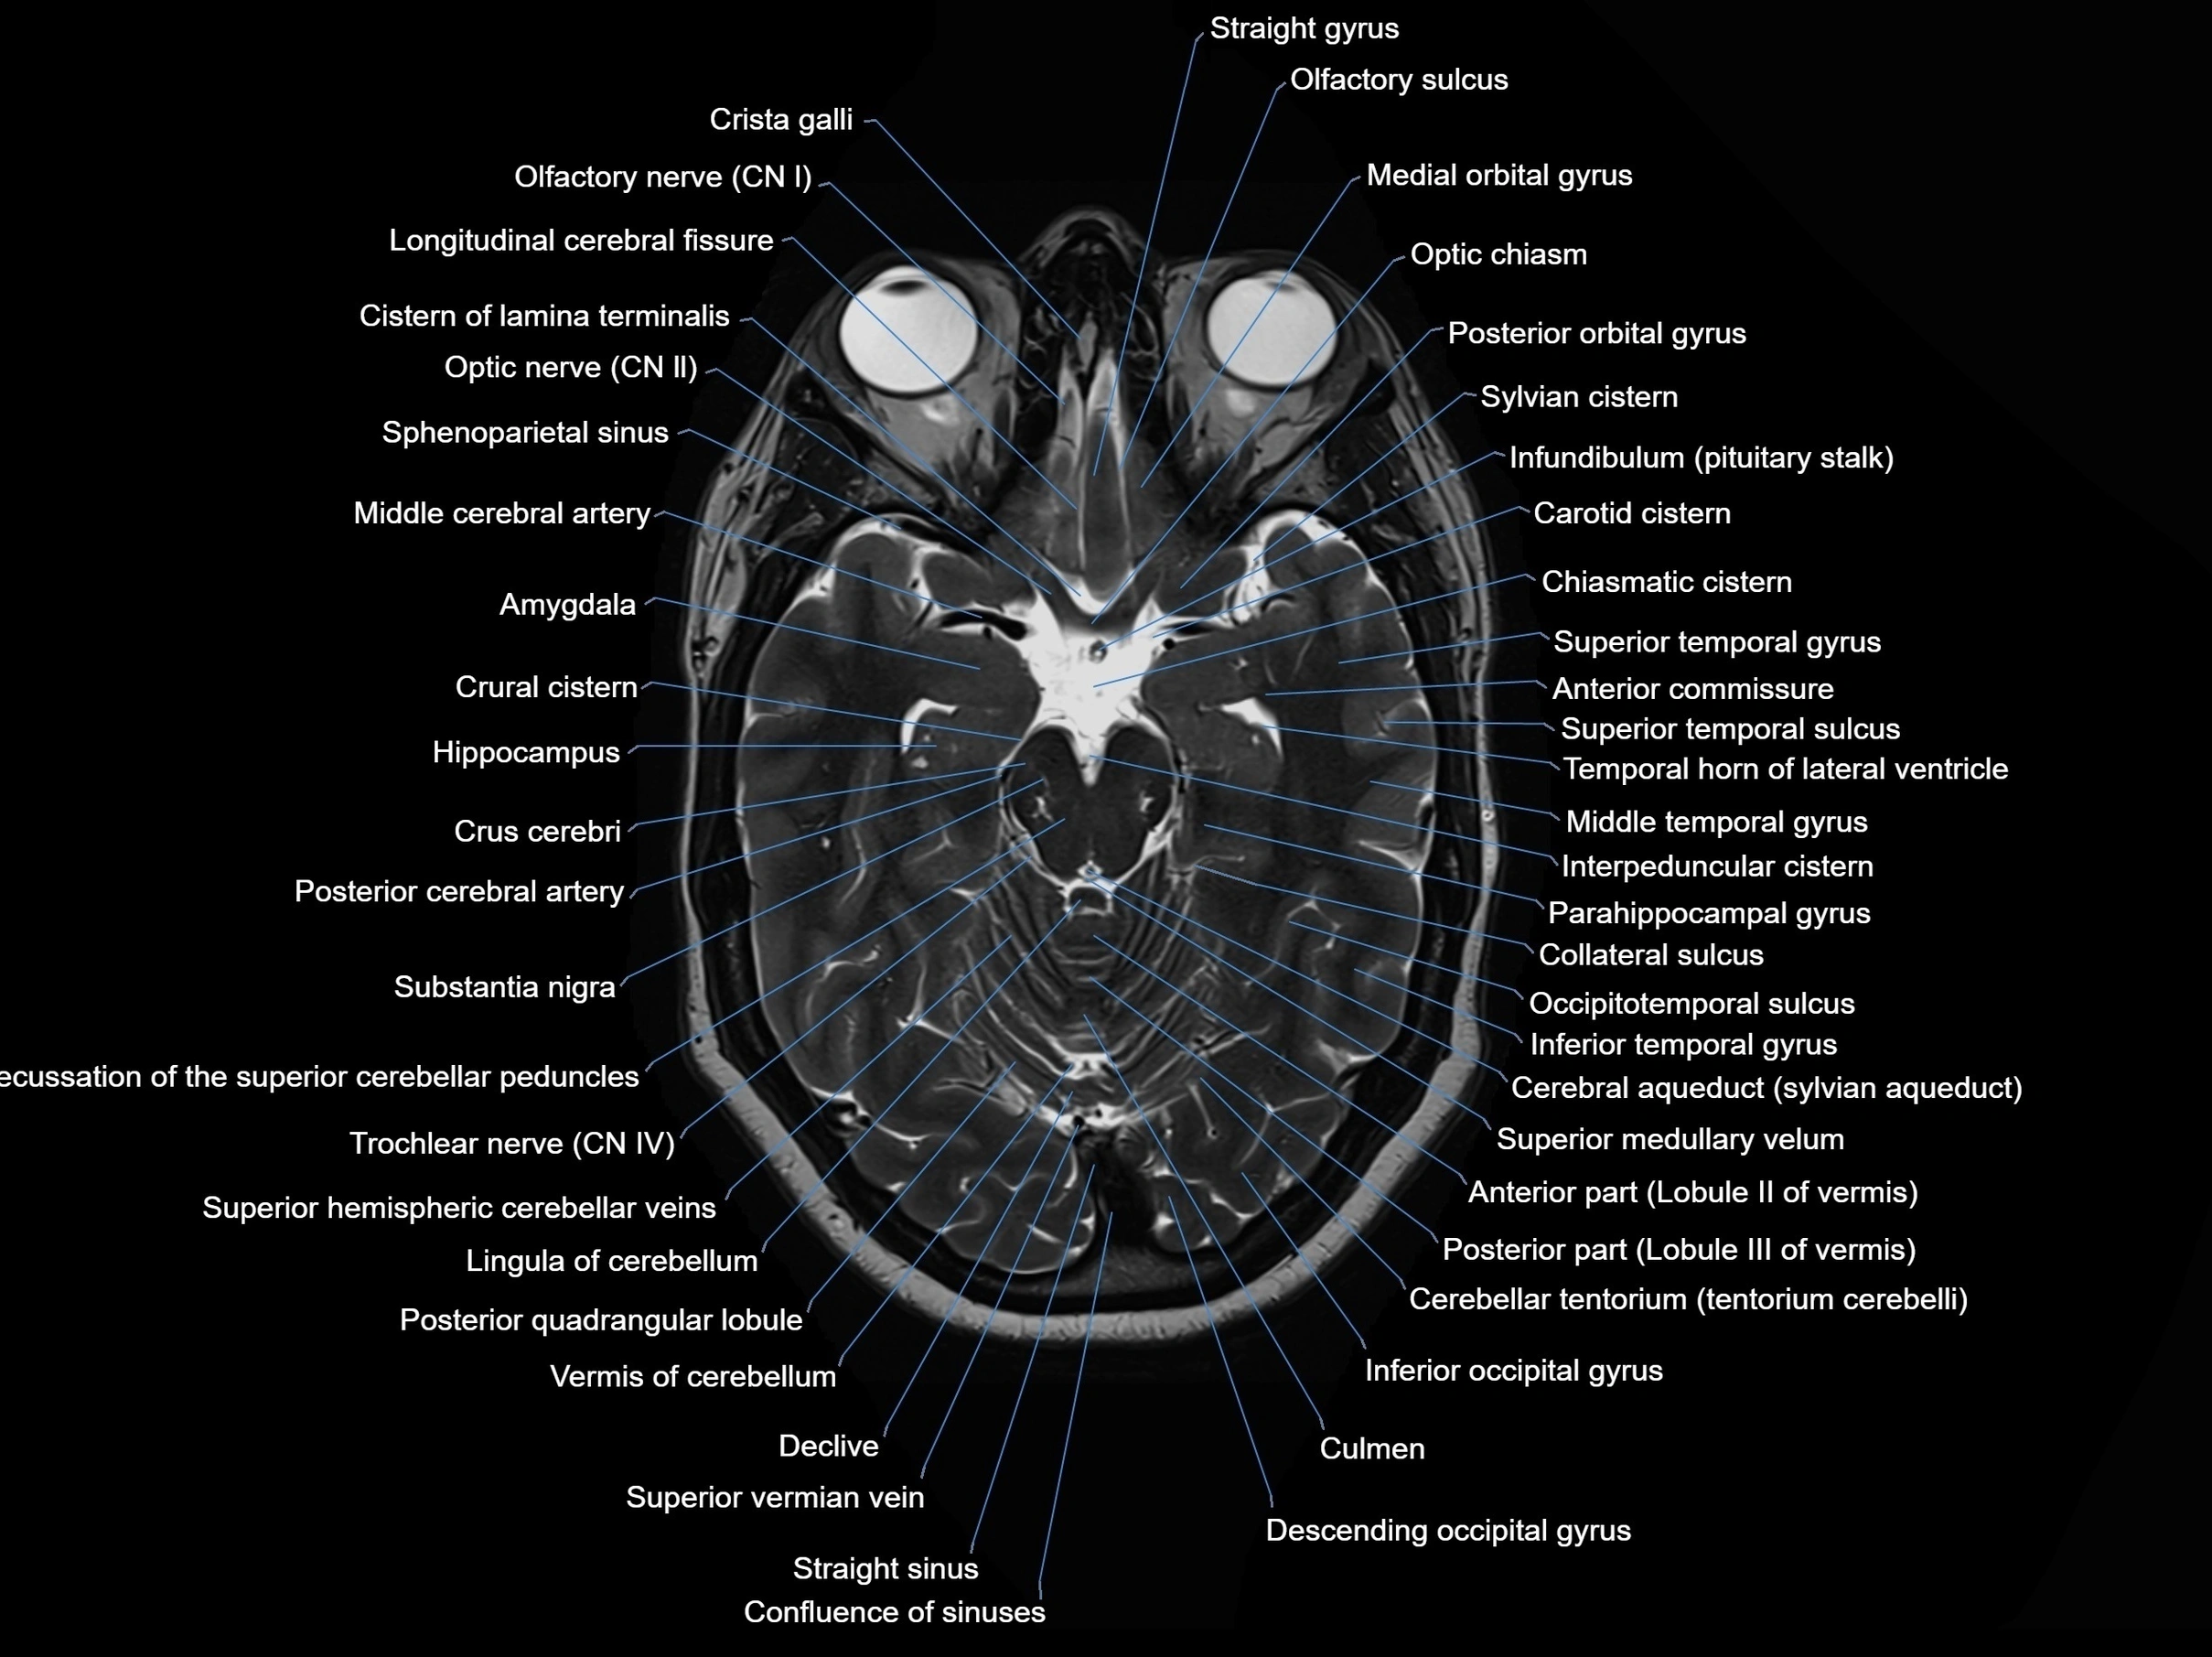

MRI images